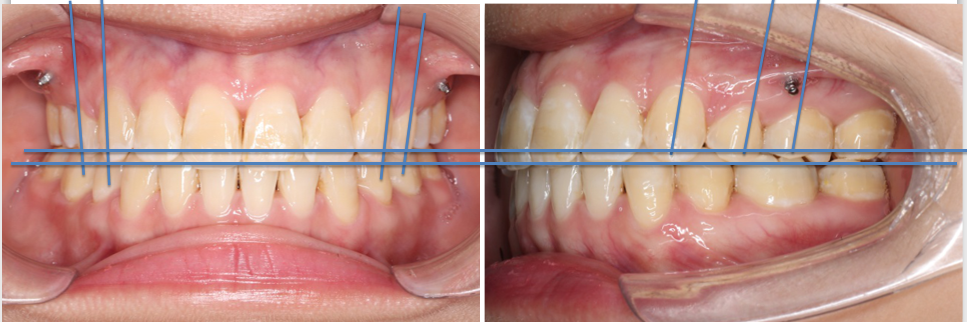

2018.11.14  术后侧面改善明显,露龈笑改善明显,笑弧笑线协调,颏部肌肉紧张度明显改善

2018.11.14  术后磨牙尖牙I类关系,中线齐,覆合,覆盖正常

宏观评价:面部对称,面下三分一比例协调,上下唇凸度正常,上颌牙列内收转矩控制良好,下颌后缩改善,颏唇沟变得更加柔和,术后达到基本直面型。

迷你观评价:上下牙齿中线与面中线对齐,笑弧协调,微笑时牙龈暴露量正常,微笑时横向正常,左右唇基本对称。

微观评价:牙齿整齐,咬合关系良好,上下前牙转矩及突度控制良好,磨牙关系I类,尖窝咬合关系良好,OB,OJ正常。